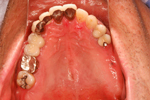

③ 上の顎 インプラント後